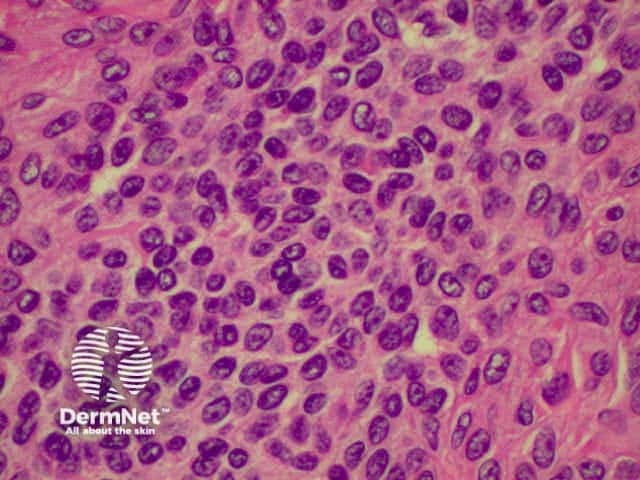

Benign and malignant tumours of inflammatory cells may involve the skin primarily or secondarily. The majority of these are lymphomas, which may be of T or B cell type. These tumours are uncommon, and only Mycosis Fungoides (a form of cutaneous T cell lymphoma- CTCL) will be described. Cutaneous T-cell lymphoma (CTCL) arises from the skin. Link to a clinical description of cutaneous T-cell lymphoma.

Mycosis fungoides is the most common form of CTCL and has several stages including patches, plaques and tumours. In early patch stage disease, it may not be possible to make a histological diagnosis of MF, and repeat biopsies as the disease progresses may be required, even when the clinical suspicion is strong.

The histological features of mycosis fungoides include: